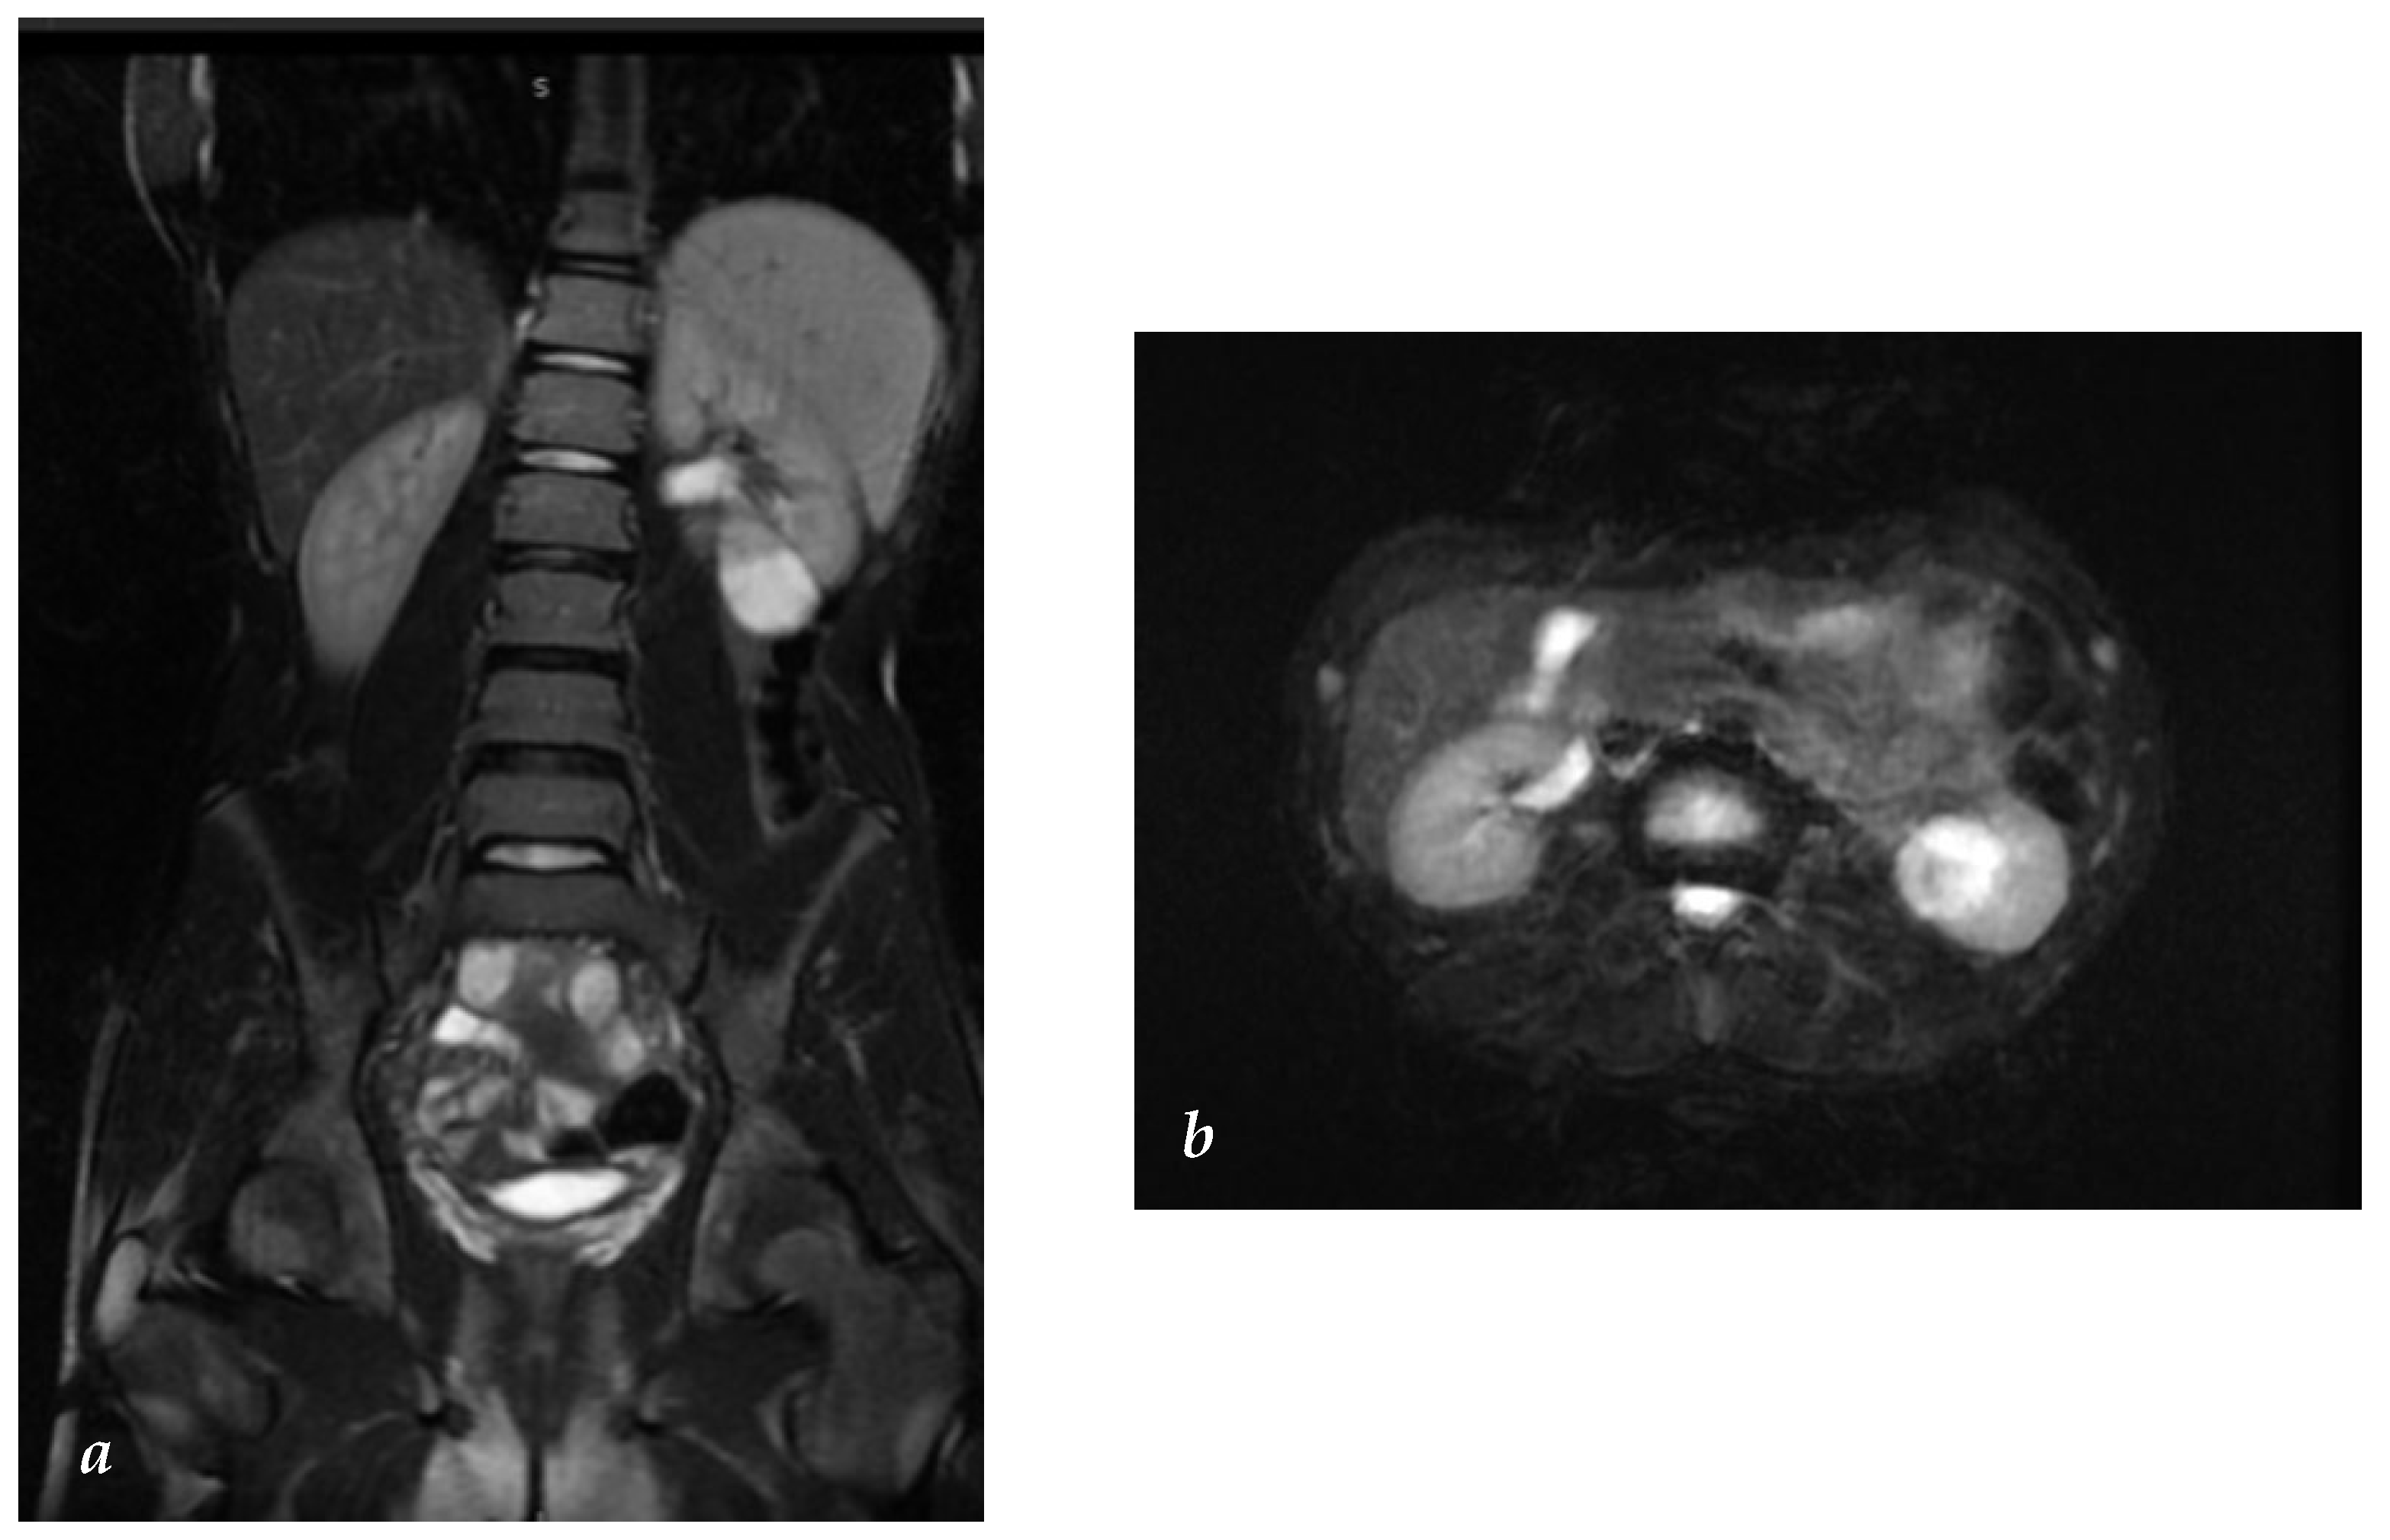

MRI was planned and, during the creatinine level measurement for the administration of an MRI contrast, complete blood count and electrolyte tests were requested, and they were within normal ranges. The MRI revealed a partially solid upper portion and a fluid-filled lower portion of the lesion in both T1 and T2 phases, resulting in the upgrade of the Bosniak classification from III to IV (Figure 2). A chest CT scan did not exhibit any suspected findings.

Figure 2. (a,b) Abdominal MRI: the coronal and transverse views exhibiting the tumor position and excluded lymph node localization.